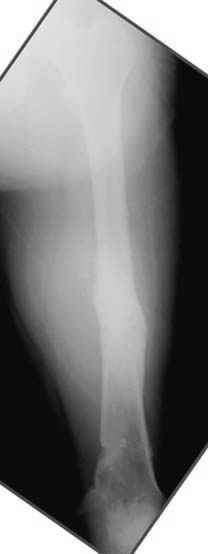

пластическая модель; и коррекция бедра аппаратом Илизарова.

Почему не замена гвоздя с рассверливанием, а аппарат?

Отправитель: Alexander Chelnokov 23 Ноябрь 2004, 21:29

хотя даже если бы и инфекция , то nail exchange с рассверливанием канала - вариант дебрайдмента) Я думаю, что последовательность развития событий:

Узкий к-м канал - тонкий гвоздь- усталостный перелом дистальных винтов - развитие нестабильности и как ее результат остеолиз вокруг гвоздя - деформация анатомической оси бедра. Похоже, что я понял почему аппарат, а не новый гвоздь:-)

ET> Я думаю, что последовательность развития событий:

[...]

ET> деформация анатомической оси бедра.

Да, наверно. Но если ничего другого нету, ту небольшую деформацию можно было устранить дистрактором одномоментно ввести другой гвоздь.

ЕТ - Изначально костно-мозговой канал бедра был узкий, дальнейшее его рассверливание ещё больше скомпрометирует прочность бедра( латеральный кортекс дистального отломка уже истончен), приведет к дефекту наружной стенки - хотя это только мои догадки - хотелось бы знать мнение Джолдаса о выбранной тактике.